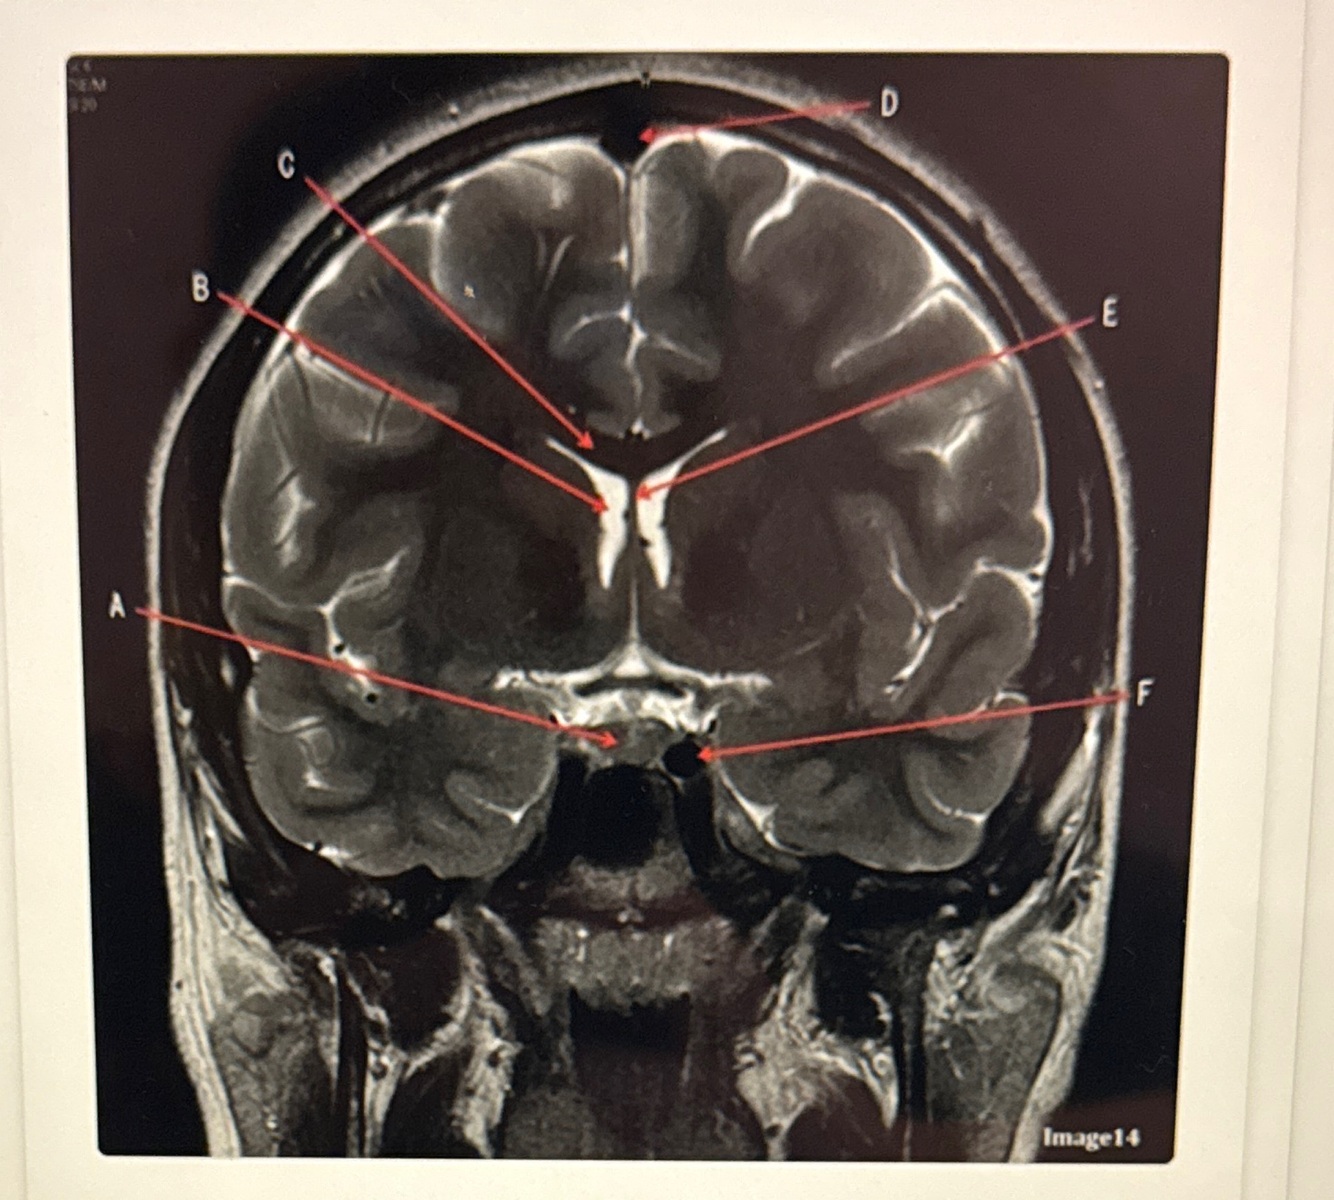

Letter A is pointing to

A

Genu of the corpus callosum

5

Q

Letter E is pointing to

FORNIX

How well did you know this?